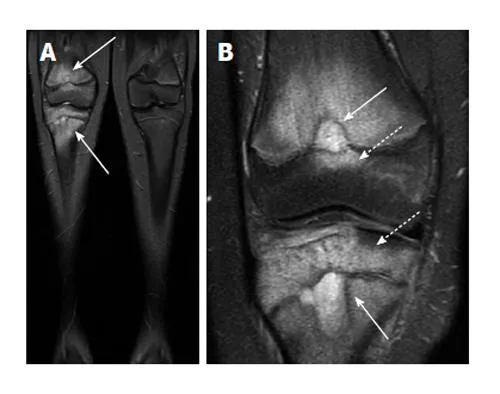

While plain radiographs suffice for most OA diagnosis, advanced imaging reveals early changes and guides interventional therapies:

MRI Assessment

⭐ Clinical Pearl: MRI is not routinely indicated for OA diagnosis but becomes essential when considering joint-preserving surgery (osteotomy, cartilage repair) or when symptoms seem disproportionate to radiographic findings-situations occurring in 15-20% of cases.